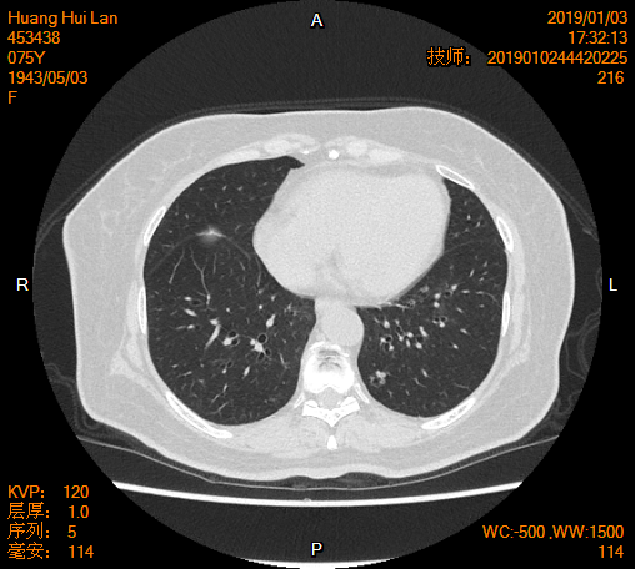

2016-04-13胸腹盆CT

2019-01-04胸腹盆CT